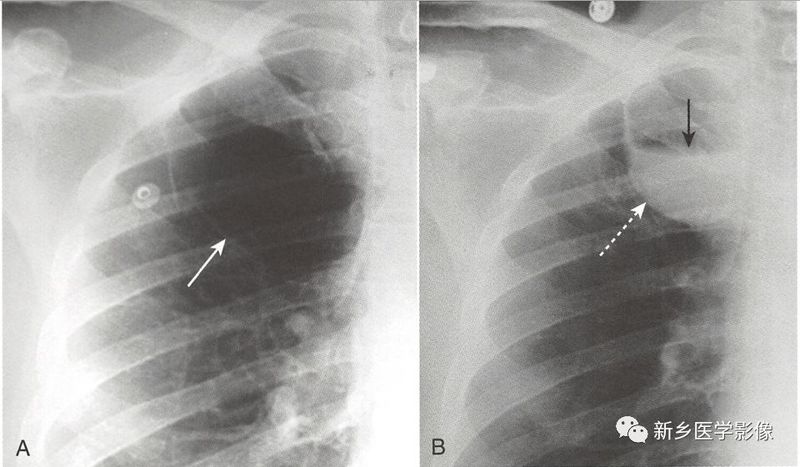

肺大疱

肺大疱多大于1cm,常与肺气肿有关,位于肺实质内,有非常薄的壁( <1mm),常规胸部平片上仅部分壁可见,在CT上更易显示

常规平片上可见局部肺纹理缺乏,由此来推断存在肺大疱。

肺大疱可增大充满单侧胸腔,受累侧肺组织被压缩似消失(肺消失综合征)。

肺大疱感染或出血可见气-液平面。